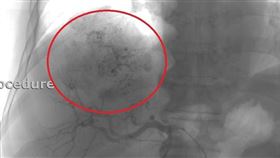

台中83歲廖奶奶7年前因吐血、腹水緊急就醫,當時肚子...

2024/07/30 10:18